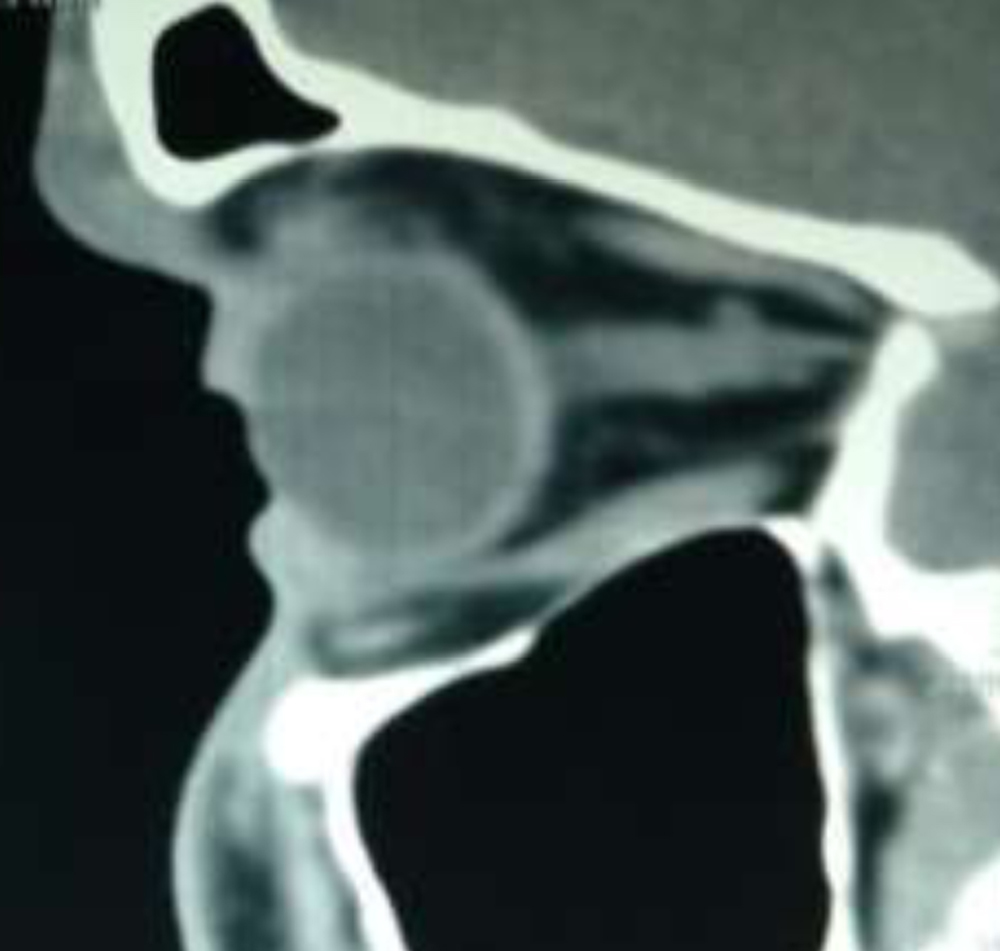

On CT Scan

A 2.2cm hyperdense Foreign Body [+107 HU] with Partial Inf rectus entrapment was seen .